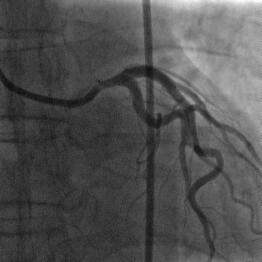

��̃P�[�X�i�ʐ^�P�C�Q�j�ŊF�Aproximal LCX total

occlusion

�Ƀ��C�A�͎h����܂���������܂���ł����B���C�A�͍ŏ���intermediate,